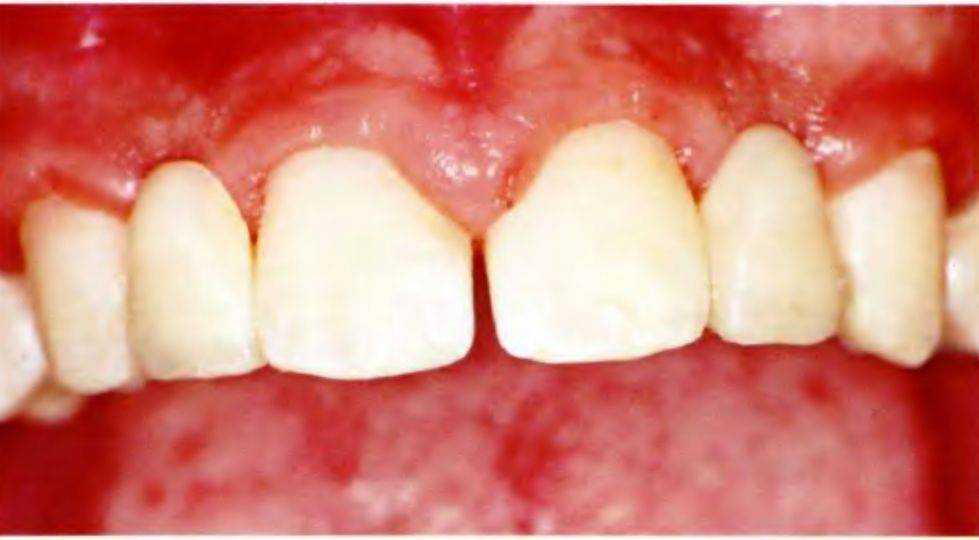

Рис. 5-Зс. Линия улыбки пациента

Рис. 5-3d. Клиническая картина после увеличения пространства ортодонтическими методами